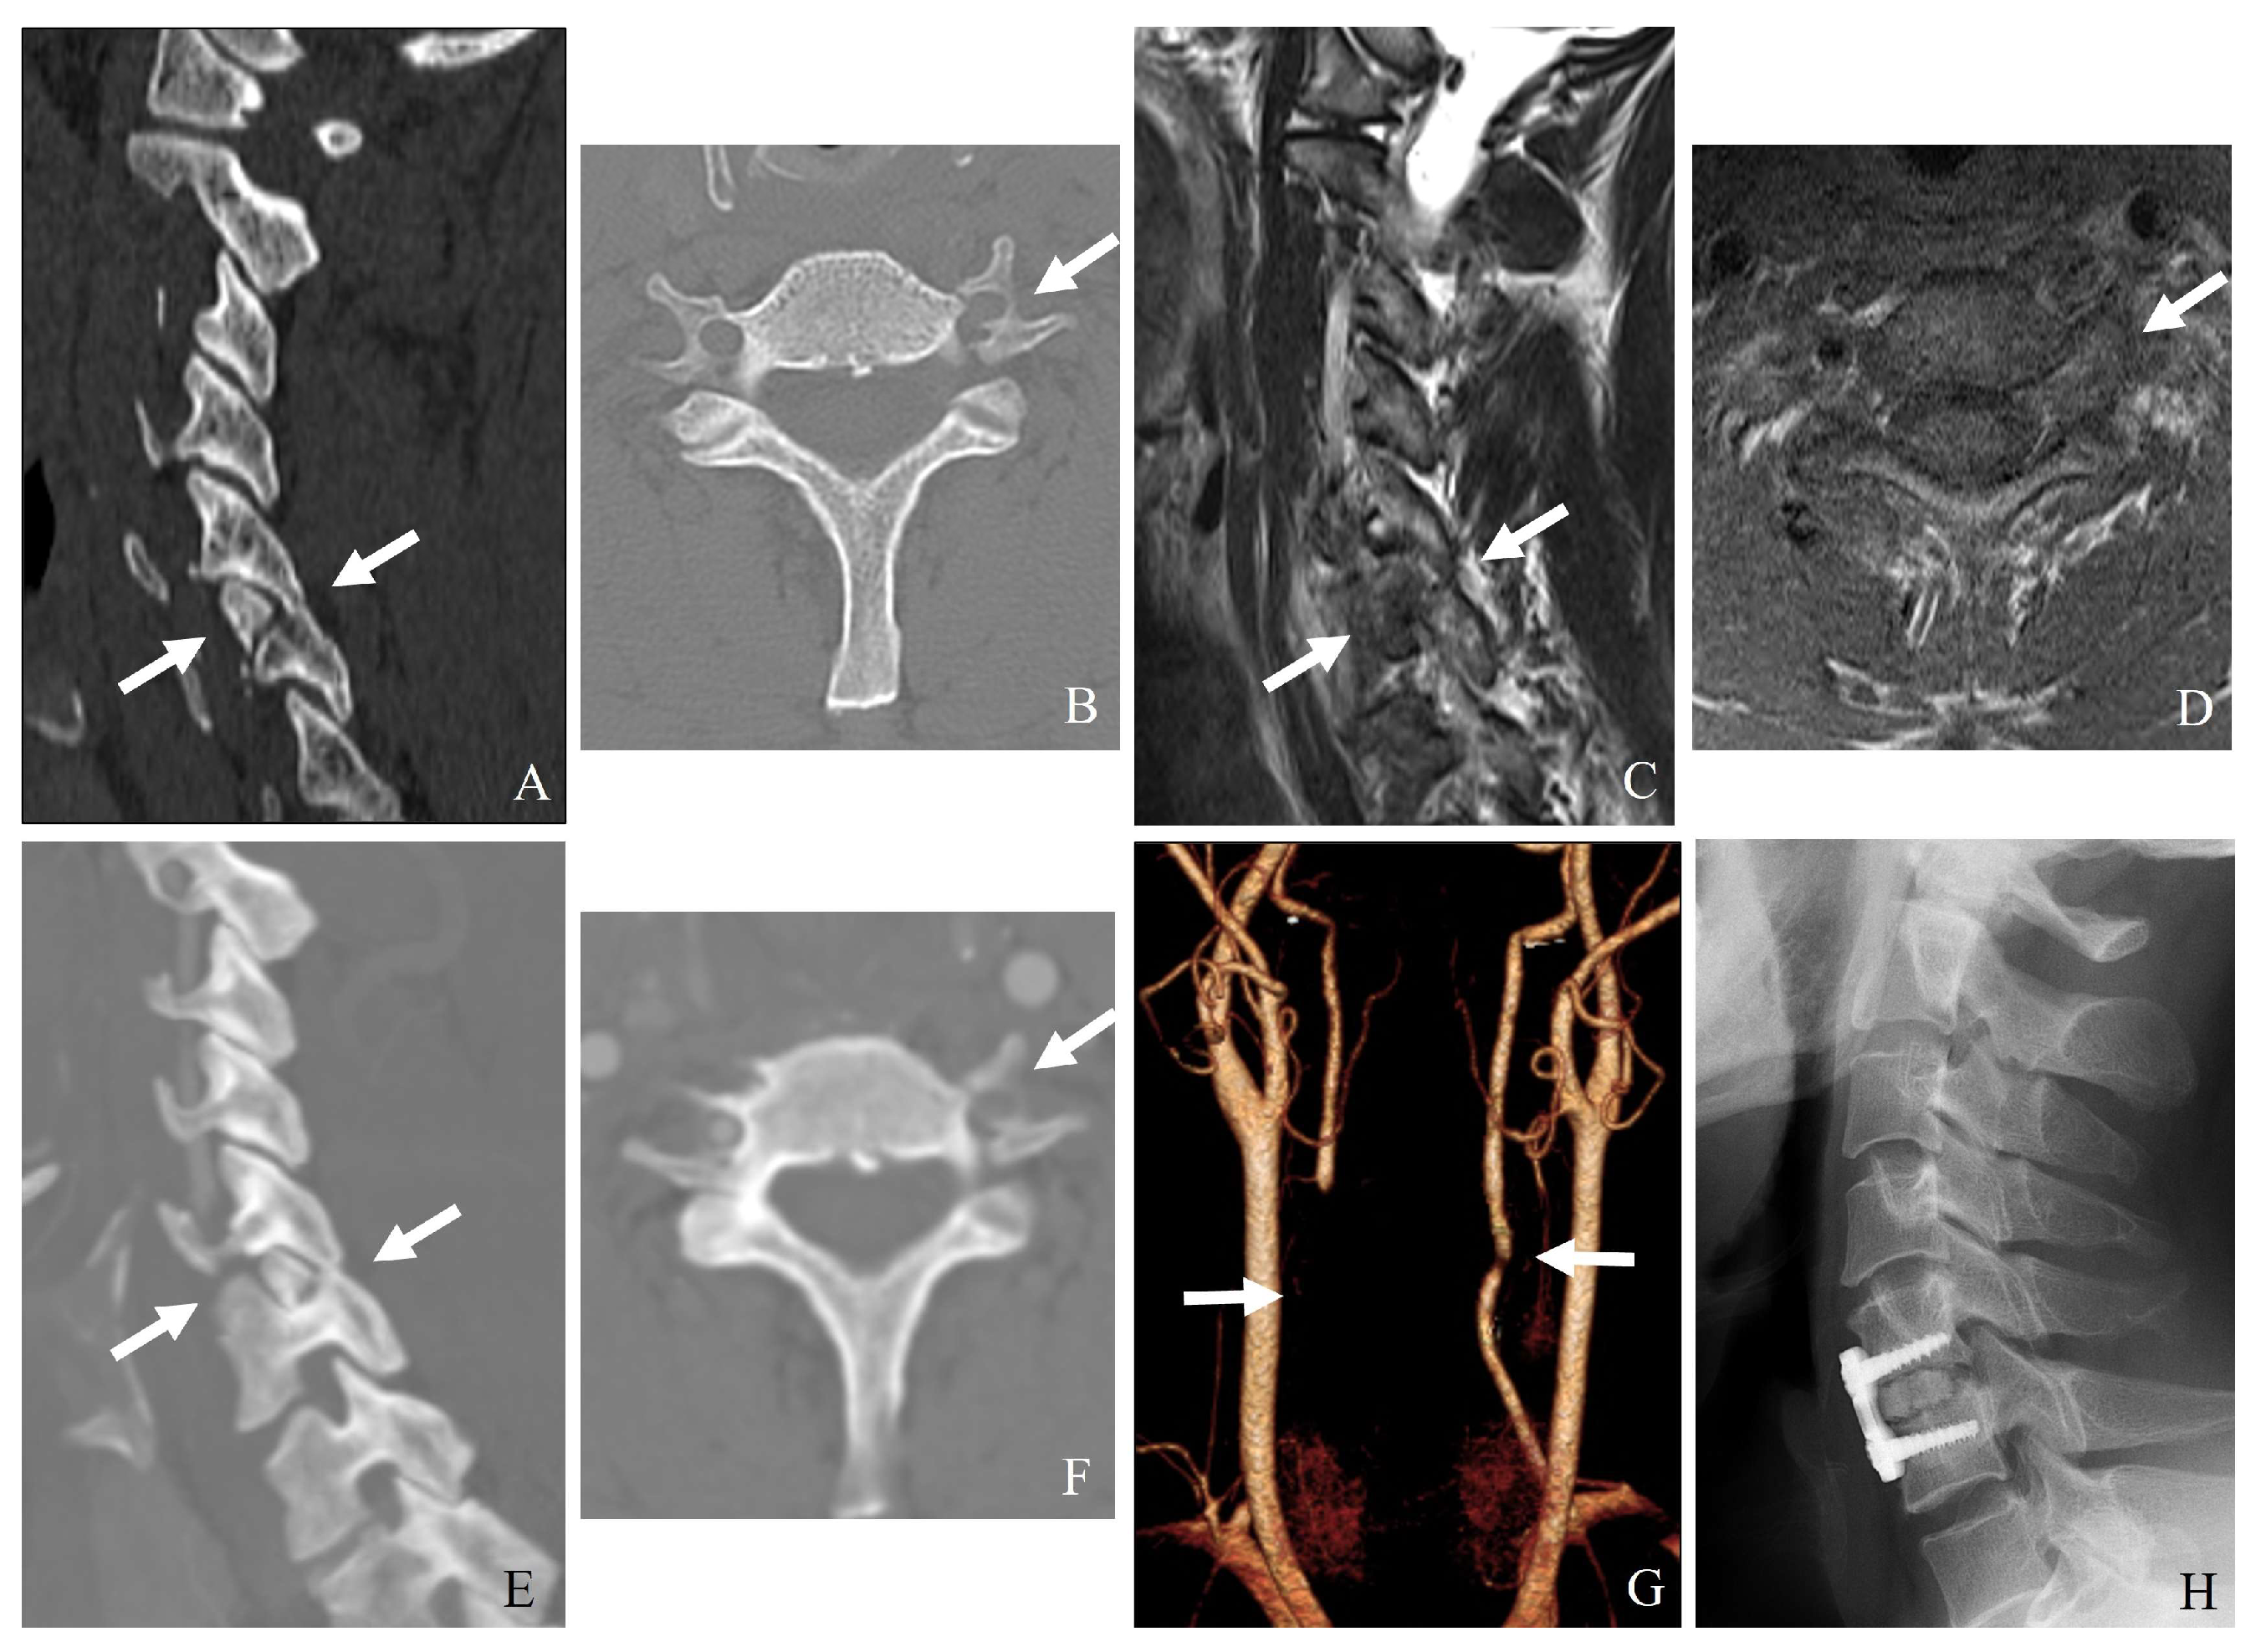

- Fracture of the lateral mass or pedicle can lead to direct bony impingement on the vertebral artery (Figure 8).

- CT angiography: The gold standard for detecting vertebral artery injuries (Figure 9).